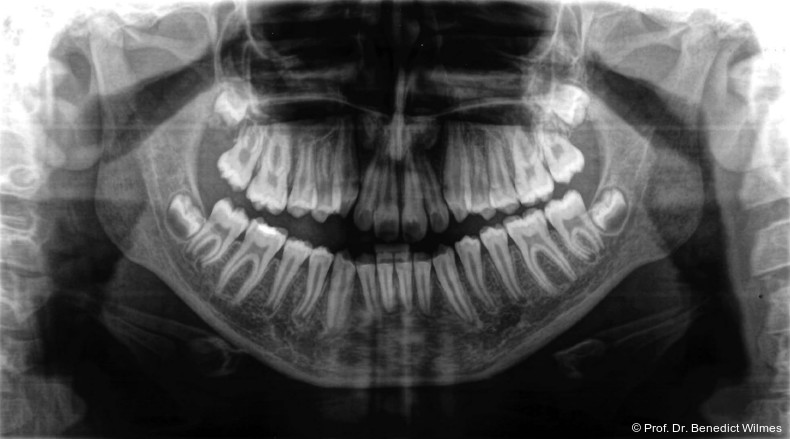

Eine 13-jährige Patientin stellte sich mit beidseitigem Kreuzbiss, einem anterioren offenen Biss und einer Angle Klasse II vor. Das viszerale Schluckmuster wurde mittels logopädischer Maßnahmen umgestellt, der offene Biss persistierte jedoch (Abb. 3a–l).

Klinisches Prozedere

Die initiale Behandlung erfolgte mit einer CAD/CAM Hybrid Hyrax zur Expansion des Oberkiefers, verankert an zwei paramedianen Miniimplantaten (Abb. 4, Benefit, 2,0 x 9,0 mm). Anstelle klassischer Molarenbänder wurden Shells (geklebte Kappen) verwendet, wodurch die beiden Schritte Separieren und Anpassen von Molarenbändern entfallen. Die Miniimplantate und die Apparatur wurden dank eines Inser­tionsguides in nur einer Sitzung eingesetzt.